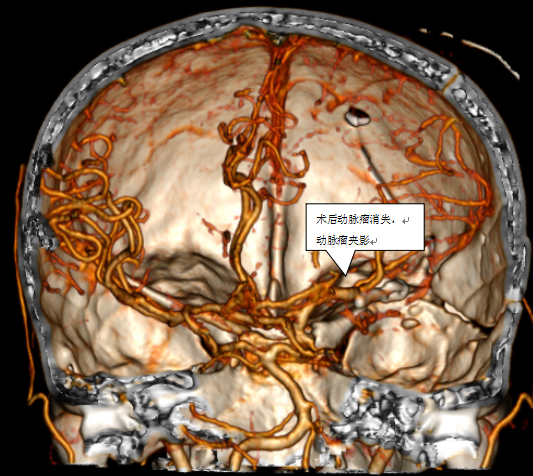

凸出位置为动脉瘤

经过充分的术前讨论并上报手术计划后,血管组组长张珩手术团队开始了手术,张珩医生在余辉主治医师及王秋实主治医师的配合下,历经1小时成功夹闭动脉瘤并清除血肿,术后经过神经外科团队的精心治疗,顺利由神经外科重症监护室转入普通病房并康复出院。